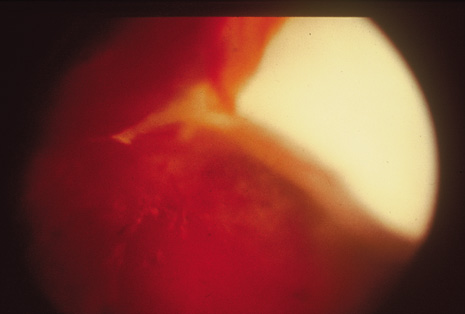

Although keratocentesis had been advocated historically as a treatment for active uveitis, it lost the attention of ophthalmologists until 1919, when Bruckner3 first examined the aqueous humor for diagnostic purposes. Laboratory techniques were revolutionized in the 20th century in areas such as: (a) evaluating very small aliquots of fluid (0.2 to 0.3 mL of aqueous or vitreous), and (b) identifying specific microbial organisms and the predominance of other cell types, antibodies, and proteins in these fluids (Figs. 1, 2, 3, 4, 5, and 6). These advancements have led to the development of diagnostic paracentesis for sight-threatening ocular inflammations that are difficult to diagnose. Witmer4 and O'Connor5 have provided strong evidence that samples of the aqueous humor reflect the antibody-producing capabilities of the iris and ciliary body, particularly when more specific antibody per unit of gamma globulin can be found on the aqueous humor than in the blood of the same patient.6–8 These determinations may be highly significant when one considers the fact that diseased tissue is being bathed in an antibody-containing fluid that is elaborated locally. For instance, in the case shown in Figure 1, the immunofluorescent antibody titer to toxoplasmosis is four times greater in the vitreous aspirate at the time of vitrectomy for repair of retinal detachment than in the plasma. These same considerations have long been recognized in syphilis of the central nervous system, wherein specific antibodies may be present in the cerebrospinal fluid but not in the blood. This is also the case with an unusual presentation of ocular coccidioidomycosis9 or toxocariasis.